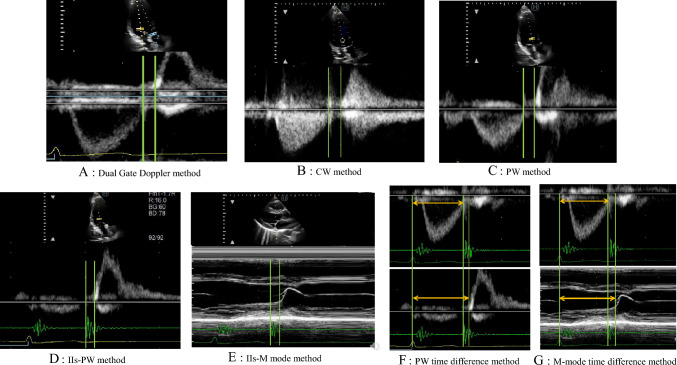

Methods: A total of 104 patients (mean age 58 ± 21 years, 48 women) were examined using ultrasound equipment with Dual Gate Doppler at our hospital. In addition to Dual Gate Doppler method, IVRTs were measured using seven different methods: pulsed Doppler (PW method), continuous wave Doppler (CW method), and other methods. The IVRT values obtained using the Dual Gate Doppler method were compared with those measured using other methods.

Results: All IVRTs measured using conventional methods showed a strong correlation with the that measured using the Dual Gate Doppler method. However, there were slight deifferences among the IVRTs depending on the method. The PW method and the PW time difference method using only the PW showed small statistical bias and were not complicated. The IVRT measured using the CW method was significantly longer than that measured using the Dual Gate Doppler method.

Conclusions: Among the conventional methods, the PW method was the simplest and most practical method for measuring the IVRT in any conditions as arrhythmias. It is important to recognize the characteristics of IVRTs based on the measurement method.